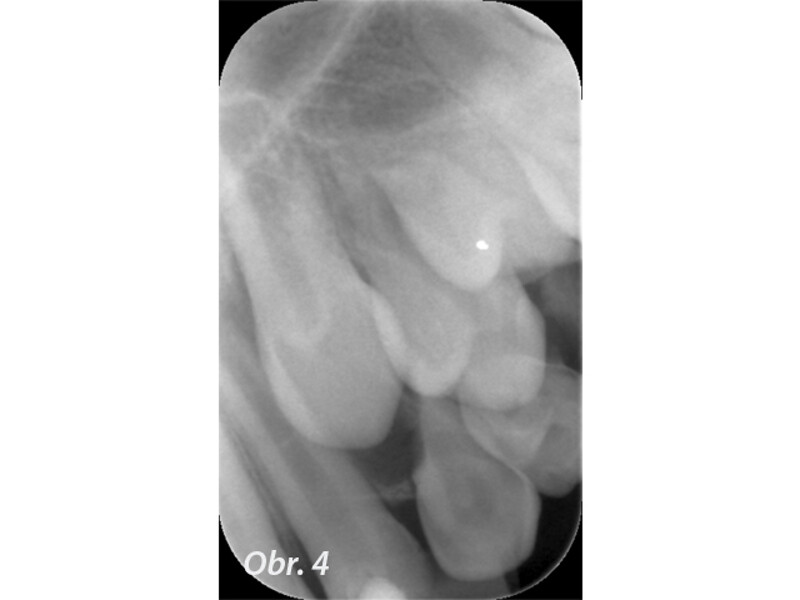

Indikační šíře MTA: Soubor kazuistik